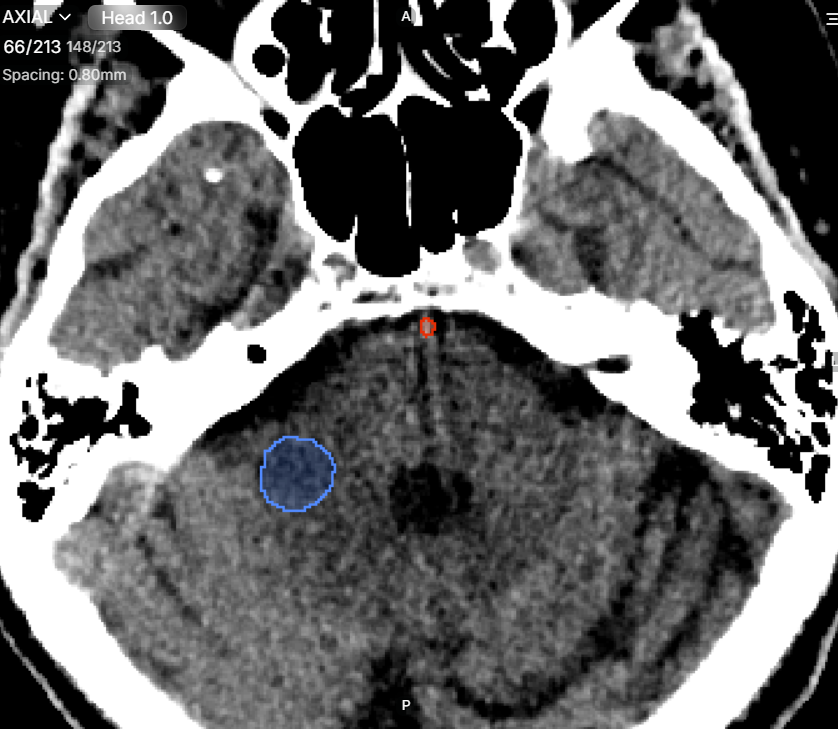

Doctors can identify diseases at an early stage with greater precision. For instance, in cancer detection, segmentation helps locate tumors and measure their size accurately.

Surgeons use segmented images to plan operations more effectively. For example, in brain surgery, knowing the exact location of a tumor helps reduce risks and improve patient outcomes.

Surgeons rely on Medical Image Segmentation to plan procedures with precision. AI-generated 3D models assist in:

- Visualizing tumors and anatomical structures.

- Reducing surgical risks by mapping critical areas.

- Improving outcomes through precise intervention.

In oncology, Deep Learning for Medical Imaging ensures accurate tumor boundary segmentation for radiation therapy. This minimizes damage to surrounding healthy tissues while targeting cancer cells effectively.